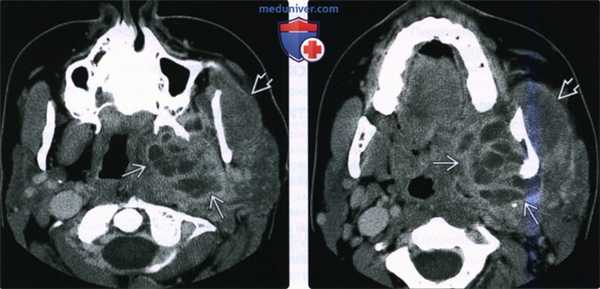

(Слева) На аксиальной КТ в костном окне у этого же пациента определяется периостальная реакция, характерная для остеомиелита нижней челюсти.

(Справа) На корональной КТ с КУ у этого же пациента определяется многокамерный абсцесс внутреннего жевательного пространства в сочетании с отеком и утолщением жевательной мышцы в наружном жевательном пространстве.

(Слева) КТ в коаном окне в аксиальной проекции у этой же пациентки. Формирование новой костной ткани в области надкостницы говорит о наличии остеомиелита нижней челюсти.

(Справа) При КТ с КУ в коронарной проекции у этой же пациентки в медиальных отделах жевательного проаранава определяется многокамерный абсцесс. В латеральном жевательном пространстве визуализируется увеличенная и отечная жевательная мышца.